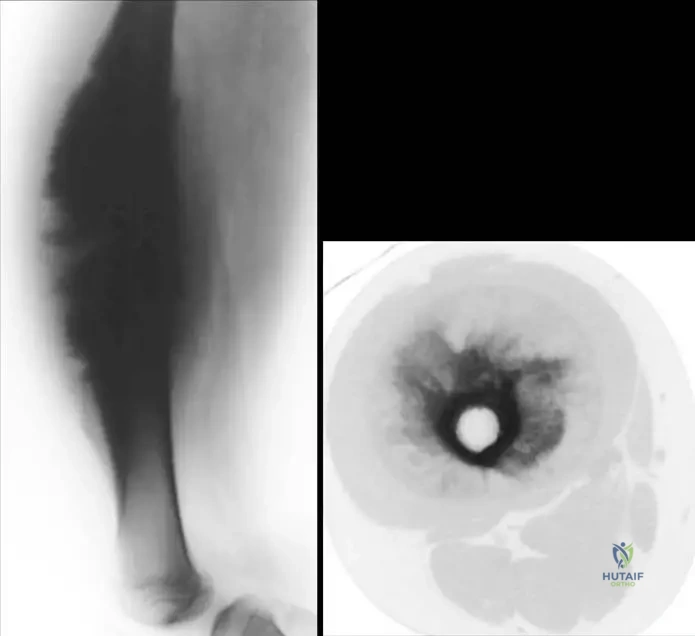

A 20-year-old male presents with a painful mass on the surface of his femoral diaphysis. Imaging reveals a high grade surface osteosarcoma. Which of the following is a key characteristic of this lesion, as shown in the provided images?

View Answer & Explanation

Correct Answer: B

Rationale: The clinical context for Fig. 8.72 states that a high grade surface osteosarcoma "forms a heavily mineralized circumferential mass that encircles the bone, but does not involve the medullary canal." This is a defining feature distinguishing it from conventional osteosarcoma which typically involves the medullary canal. Option A is incorrect because it states medullary involvement.